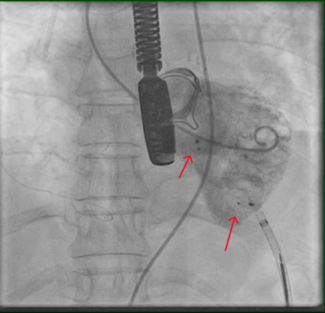

Therapy with 325 mg aspirin, loading 600 mg clopidogrel, and 5.000 IU unfractionated heparin was started, and the patient was immediately transferred to the catheterization laboratory. Coronary angiography showed total occlusion of mid left anterior descending (LAD) coronary artery, with thrombolysis in acute myocardial infarction (TIMI) 0 flow as shown in Figure 2. After vessel  wiring through an Extra Back Up 6 Fr guiding catheter (Medtronic), an aspiration catheter (6 Fr Export AP; Medtronic) was inserted. The blood clot was successfully aspirated with immediate relief of pain and resolution of ST segment elevation. TIMI III flow was restored with no residual lesions at the site of thrombus or the distal parts of the vessel (Figure 3). A decision was made not to deploy a balloon or a stent in the affected area. Left circumflex and right coronary arteries were normal, as detected 1 year before.

wiring through an Extra Back Up 6 Fr guiding catheter (Medtronic), an aspiration catheter (6 Fr Export AP; Medtronic) was inserted. The blood clot was successfully aspirated with immediate relief of pain and resolution of ST segment elevation. TIMI III flow was restored with no residual lesions at the site of thrombus or the distal parts of the vessel (Figure 3). A decision was made not to deploy a balloon or a stent in the affected area. Left circumflex and right coronary arteries were normal, as detected 1 year before.